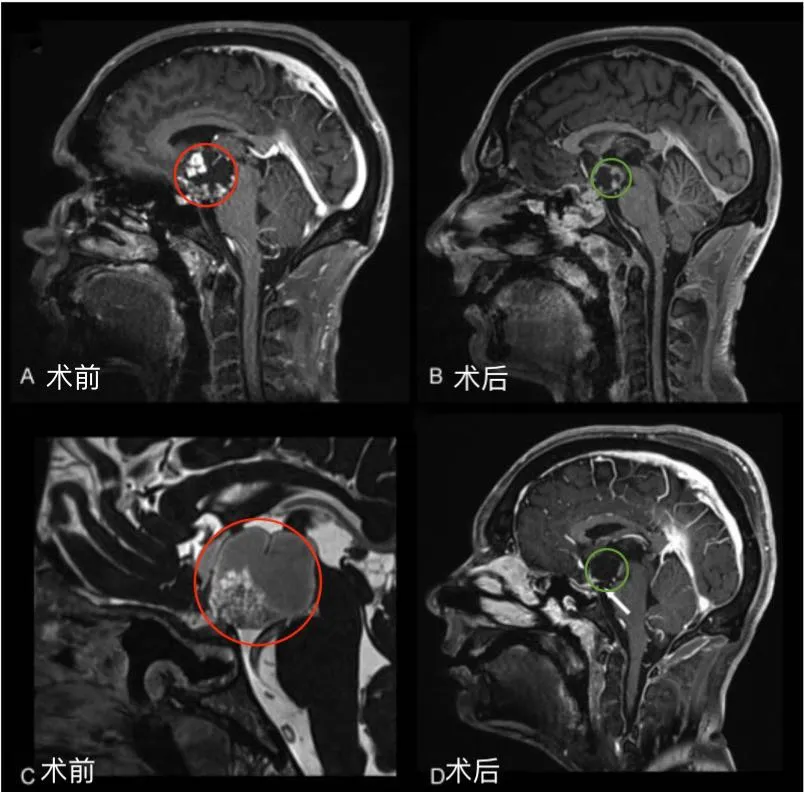

圖1后視交叉性顱咽管瘤患者腫瘤術(shù)前(A,C)和術(shù)后(B,D)矢狀位增強(qiáng)MR對比,顯示腫瘤全切